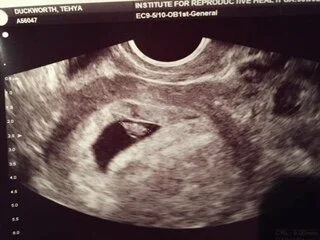

Then came the hard part:  waiting for the pregnancy test.  I know I drove my friends crazy while I waited.  And I totally didn't wait like I was supposed to.  I was testing early on and knew days before the blood test that it would be positive.  Still, I nervously awaited the rests.  118.  That was a Friday.  The number needed to at least double by Monday.  This is where things always went wrong before.  We never passed the second blood draw.  Our numbers always dropped.  And even though we "took the ferry instead of the tunnel" as my husband put it and things were different than before, my heart was choked with fear.  Usually I can dream big and imagine grand outcomes.  My heart would not allow it and I could not even imagine a world where those numbers would double.  And yet they did. 380.  And for the first time I began to feel hope for our child.  The next step was the ultrasound at 7 weeks.  Here they would determine how many babies I was carrying, and they would look for the heartbeat, measure, and determine a due date.  After reading account after account of women going in and there being no heartbeat I was once again gripped with fear.  We prayed.  Friends prayed.  I specifically asked for strong pregnancy symptoms to reassure my heart that all way well.  And that prayer was answered.  My husband and I made an agreement that I was not allowed to complain about my symptoms and instead we would give praise to the Lord for answering our prayers.  At that first ultrasound I was sick with worry, but for no reason.  Within seconds we could see the heartbeat flicker on the screen.  131 beats/minute.  perfect.  The doctor hooked up the audio and we could hear it.  I can't describe the elation in our hearts at that sound.  I was scheduled to come back at 10 weeks to check on progress and to graduate to the normal OB doctor.

4 days later we had an unwelcome development.  I had started bleeding.  Having never had any bleeding or spotting with my surviving children, I was convinced I was miscarrying.  It was a beautiful weekend.  I had got up, exercised, grocery shopped, did yard work, and we were hosting a cook out.  I have several other people over when it started.  I withdrew to my room for a spell, and reemerged after I composed myself.  The evening was winding down and we tried to enjoy the last moments with our company.  As soon as they left I retired to my bedroom.  My husband got on the phone with the doctor, and our 16 year old daughter cleaned up the aftermath of the party.  The doctor was not too concerned based on our description.  He said it was quite common and usually doesn't mean anything other than I may have overdone it a little.  He suggested taking it easy and said to come in for an ultrasound during the week if it continued.  I was slightly relieved, but very much on edge.  My husband put me on full bedrest for the remainder of the weekend, and I did not object.  Friends and family were enormously caring and helpful during those scary days.  The bleeding did subside, but spotting persisted.  We went in for another ultrasound and there was our little gummy bear, with heart as strong as before.  They had no explanation for the bleeding but said to keep them informed.  The following week, the spotting continued and we went in again for reassurance.  I am so thankful for the doctor's office for the support they gave.  They did not protest my insistence on multiple scans and were very understanding of the fear we felt.  They treated us with great compassion and dignity.  Once again all was well and we even got to see the baby wiggle.  The doctor then suggested that it could be from what's called a subchorionic clot, which is where the sac separates a little from the uterine wall, but could not tell from the ultrasound as it could be too small to see.  He still wanted to see me again at the 10 week mark, which was only a week away.  At 10 weeks, we came in and once again everything looked great.  The spotting was mostly gone by then and he could finally see a subchorionic clot.  He pointed it out and said it was "well-organized" or healed.  It was such a relief to have an answer, to have the complication resolved, and to see our little one and its heartbeat once more.  And at this ultrasound our baby had moved from simple wiggling to total dance party boogying!!  Doctor exclaimed, "that is an active one!!"  Sounds like we will have our work cut out for us.